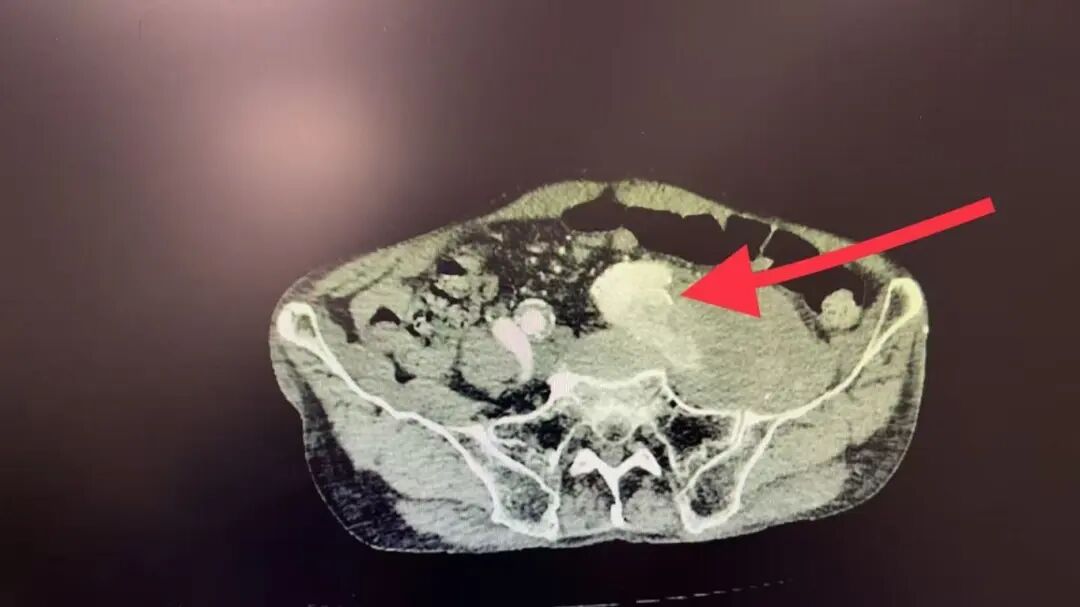

“患者入院时情况很严重,左侧髂动脉瘤已破裂出血,形成血肿压迫髂静脉,导致左腿严重肿胀。”血管外科医护团队回忆,破裂位置位于髂内动脉,且血管严重扭曲,如同被乱麻堵住的管道,让手术难度倍增。

血管破裂后,内部结构混乱,真正的血管通道,也就是真腔,被压得像一条缝隙,而假腔和血肿空间很大,导丝稍有不慎就会走错路,一旦进入假腔操作,可能导致破裂加剧。手术团队凭借丰富的经验,成功将导丝精准送入了真腔。

破裂点位于髂内动脉的起始部,这是一个关键的血管岔路口。手术团队要用覆膜支架封住破口,但这个补丁会同时堵住髂内动脉的入口。为避免后续血流冲击导致新的问题,手术团队要先将这个分支血管安全地废弃掉。因此,团队先精确栓塞了左髂内动脉,再成功植入覆膜支架,完美覆盖了破裂点,恢复了主干血流的通畅。